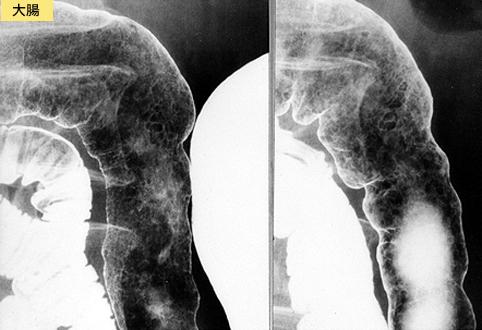

A case of intestinal amyloidosis which showed a diffuse coarse mucosa.

Inflammatory or ulcerative disease / lesions/Amyloidosis

Large intestine(Colon)/Transverse colon

X-ray